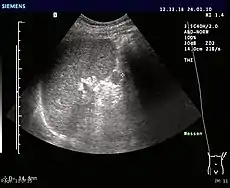

CT scan of an accessory spleen (circular object in center of image) between the spleen and left kidney.

Accessory spleens may undergo hypertrophy after splenectomy[15] Very rarely, it may cause bleeding (pictured).[16]